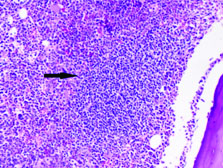

Complete blood count and peripheral smear showed thrombocytopenia and 53% abnormal cells which resembled lymphoblast [Table/Fig-1,2]. Bone marrow aspirate smears were dilute and showed 43% abnormal lymphoid cells which were medium to large sized with high N:C ratio dense nuclear chromatin, scant cytoplasm and few showing irregular nuclear margins and inconspicuous nucleoli [Table/Fig-3,4]. Trephine biopsy showed interstitial and paratrabecular infiltration by abnormal lymphoid cells which were medium sized with dispersed nuclear chromatin and irregular nuclear margins along with few interspersed large cells with convoluted nucleus showing 1-2 prominent nucleoli [Table/Fig-5].

Interstitial abnormal lymphoid infiltrate in bone marrow biopsy (40X Hematoxylin and Eosin stain).